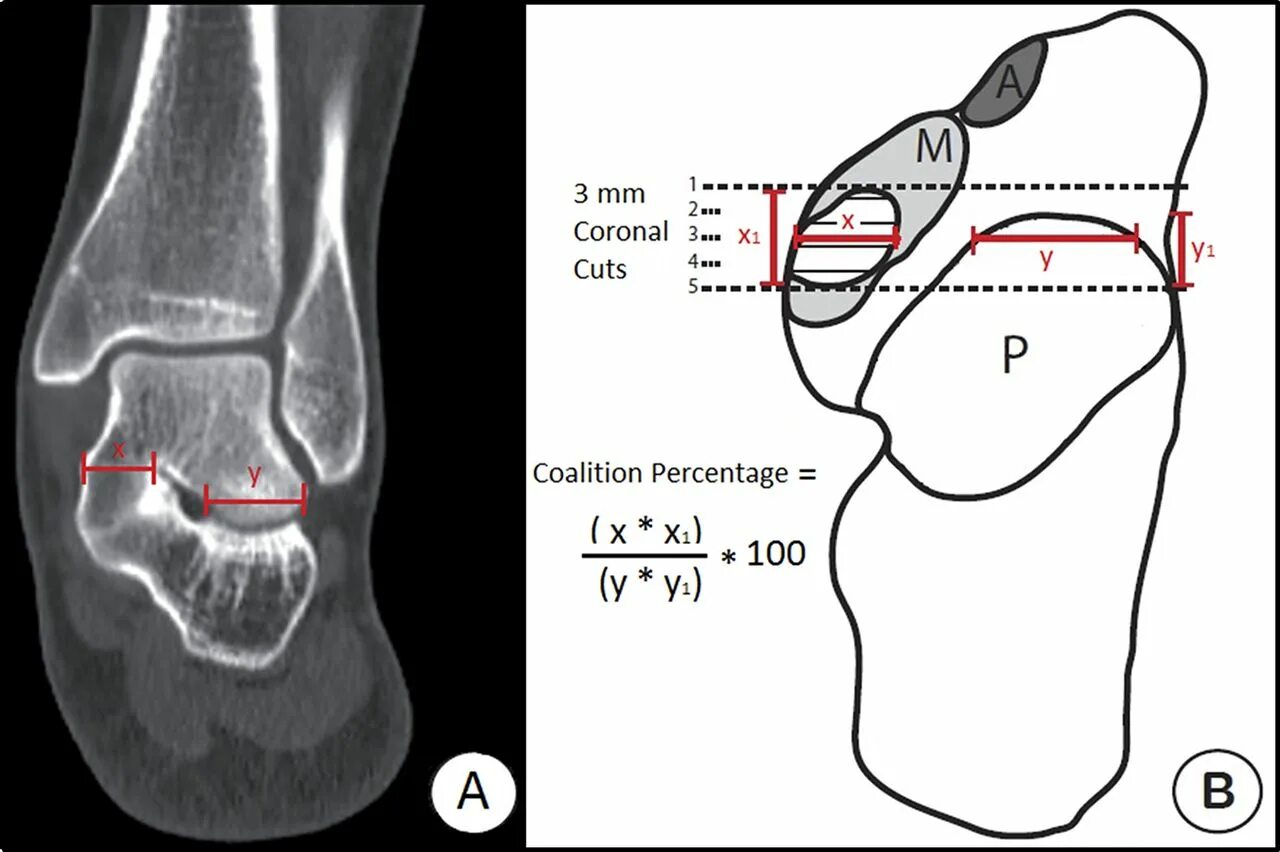

Пяточная остеотомия